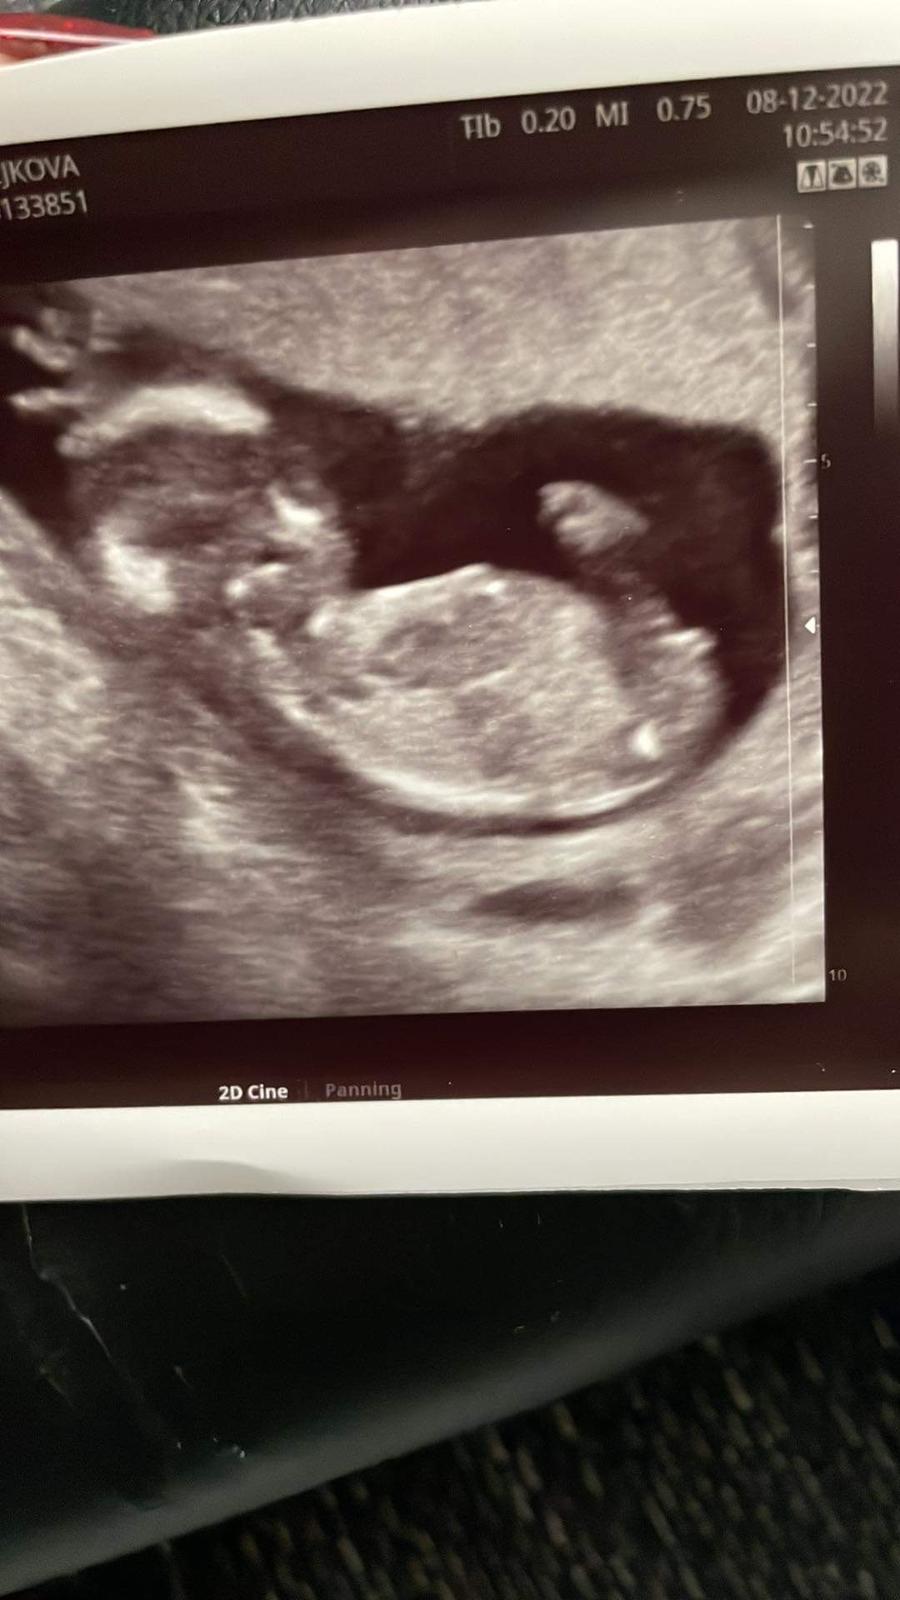

bude to prosím holčička nebo chlapeček?

Těhotenství ve 14+1.

podle fotografie je to pravděpodobně holčička, ale s jakýmikoliv nákupy a zařizováním určitě vyčkejte na ultrazvuk v 20. týdnu. Informaci berte jako orientační. 🙂